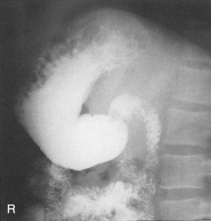

The air-barium distribution within the stomach and large intestine changes with various body positions. By knowing these distribution patterns, one can determine in which body position a radiograph was taken. Air always rises to the highest levels, and the heavy barium settles to the lowest levels (air is black, barium is white).

The fundus is located more posteriorly; therefore in the supine position it would be the lowest portion of the stomach and would be filled with barium.

In both prone and erect positions, the fundus would be filled with air as seen on the drawings below, with a straight air-barium line on the erect.

Fig. 9-31 AP supine Trendelenburg, upper GI (stomach) (Trendelenburg position best demonstrates hiatal hernia).